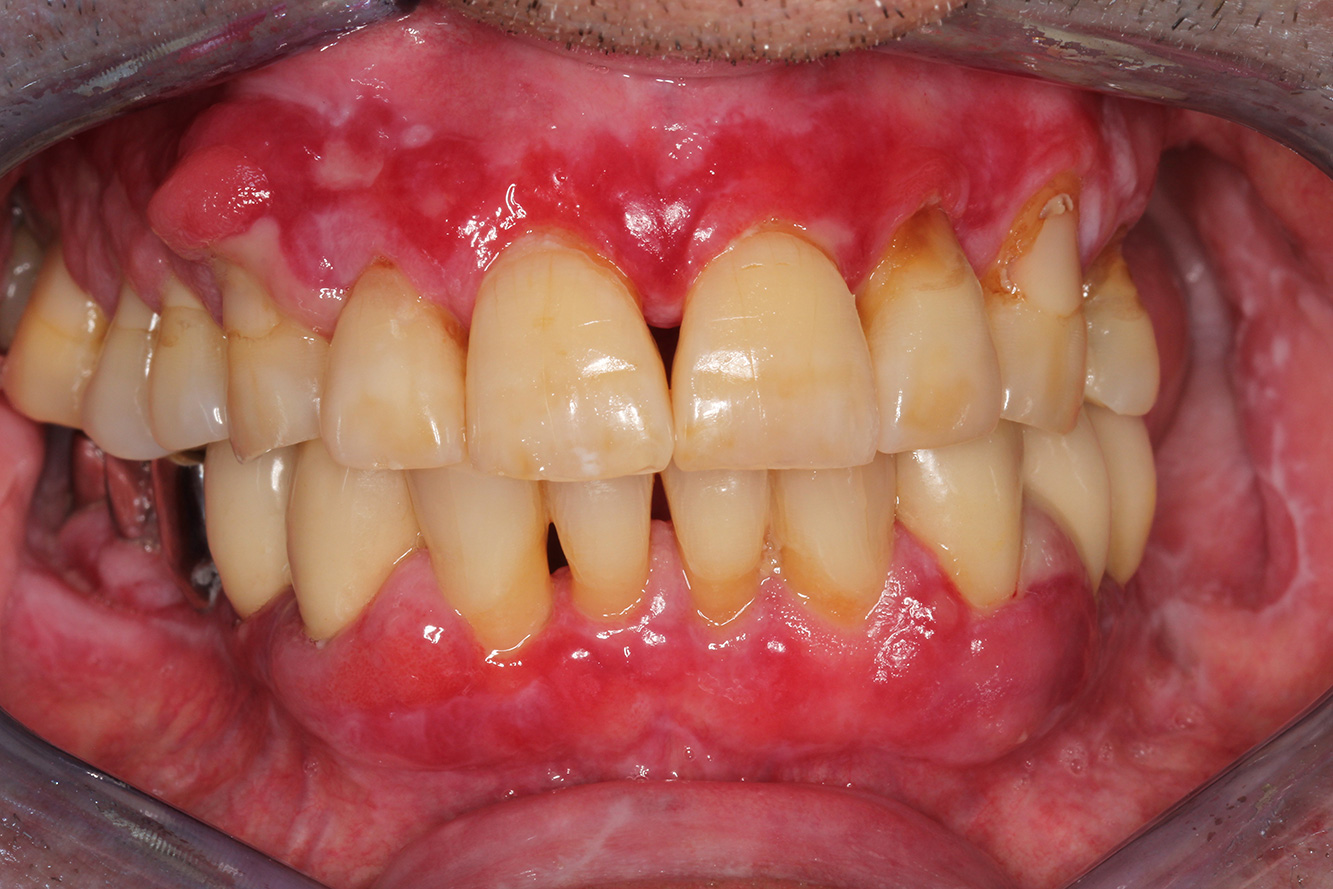

Il paziente trapiantato con iperplasia gengivale

Si presenta un paziente di 71 anni che ha subito un trapianto di reni e con anamnesi di ipertonia (ipertensione). Considerata la sua storia clinica, serve una terapia a lungo termine con ciclosporina che ha un effetto immunosoppressivo e amlodipina che è specifica contro l'ipertensione. Il paziente riporta anche gengive sensibili e sanguinanti. Per quanto riguarda invece lo stato di salute orale, il paziente ha un restauro, presenta un'iperplasia gengivale marcata, una parodontite allo stadio II, grado B con tasche attive e un'iniziale carie radicolare al dente 22 e in più mancano otto denti. Dalla valutazione del rischio di carie si evince un rischio moderato di carie (API 60). Per la seduta di profilassi si possono formulare i seguenti consigli per il trattamento. di più